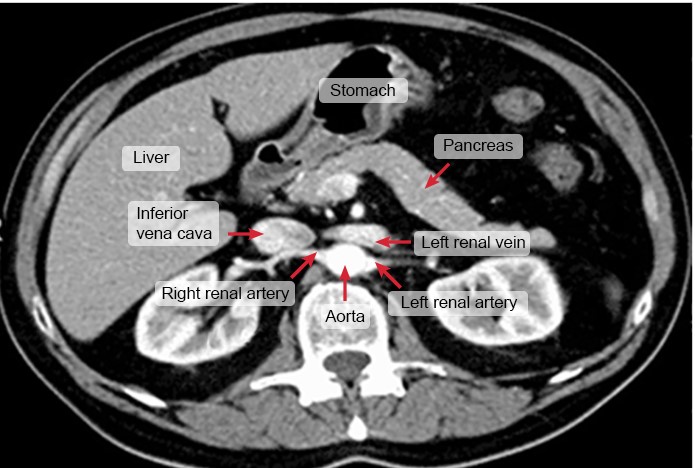

A 52-year-old man is being evaluated for nonspecific, chronic abdominal pain. As part of the workup, he undergoes an abdominal CT scan with intravenous contrast, which reveals no significant findings. An axial image from the scan is shown below.

Which of the following statements best describes the structure indicated by the arrow?

This axial CT image reveals the abdomen near the L1 vertebral level. At this level, the inferior vena cava (IVC) lies just anterior to the right renal artery and to the right of the aorta. The IVC is formed by the union of the right and left common iliac veins at the level of L4-L5 and drains into the right atrium just above the level of the diaphragm at T8. The IVC returns venous blood to the right atrium from the lower extremities, portal system, and abdominal and pelvic viscera.

(Choice A) The thoracic duct drains lymph from the entire left side of the body and all regions inferior to the umbilicus (including the entire gastrointestinal tract). It enters the thorax through the aortic hiatus and empties into the left subclavian vein near its junction with the internal jugular vein.

(Choice B) The cystic duct drains bile from the gallbladder into the common bile duct. The gallbladder is typically visualized just below the liver in the anterior right abdomen but is not well seen in this image.

(Choice C) The image reveals the abdominal aorta giving rise to the right and left renal arteries at the L1 vertebral level. The abdominal aorta lies posteromedial to the IVC within the abdomen.

(Choice E) The superior mesenteric vein joins the splenic vein to form the portal vein. The portal vein can be seen vaguely near the head of the pancreas in this cross-sectional image.

Educational objective:

The inferior vena cava is formed by the union of the right and left common iliac veins at the level of L4-L5. The renal arteries and veins lie at the level of L1. The inferior vena cava returns venous blood to the heart from the lower extremities, portal system, and abdominal and pelvic viscera.